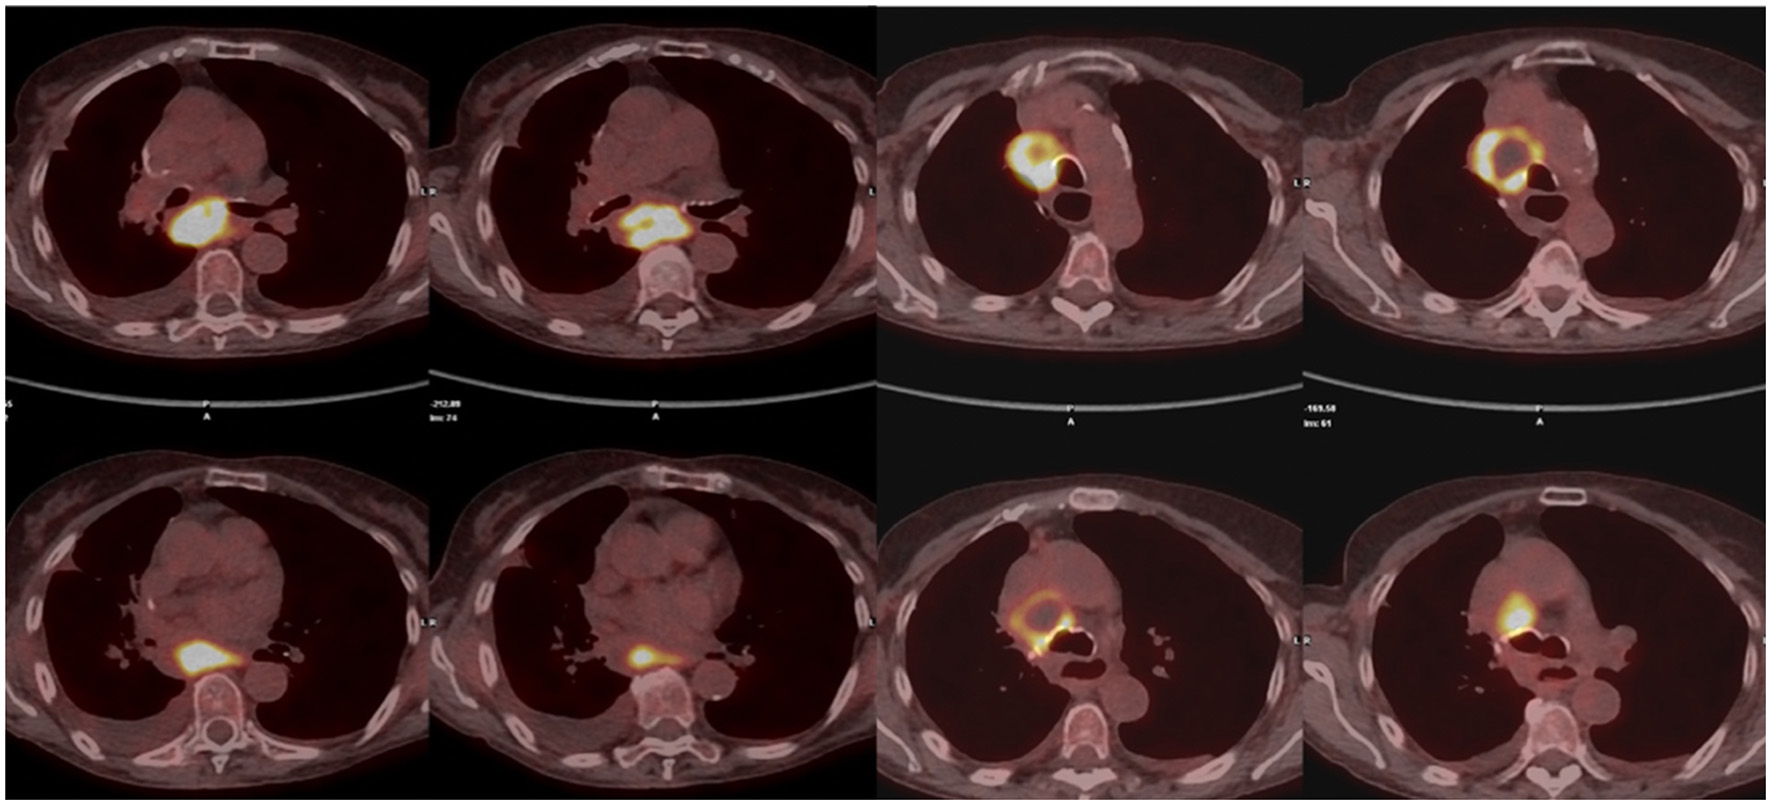

During follow-up, all these patients were referred to “Ospedali Riuniti di Ancona” (n = 7) and “Ospedale San Martino” (Genoa) (n = 1) Interventional Pulmonology Units for the characterization of new onset hilar and/or mediastinal lymphadenopathies detected by imaging with CT LN enlargement (Figure 1) and intense metabolic activity on PET/CT (Figure 2).

Figure 2

Subcarinal (7) and right inferior paratracheal (4R) FDG-PET positive lymph node.